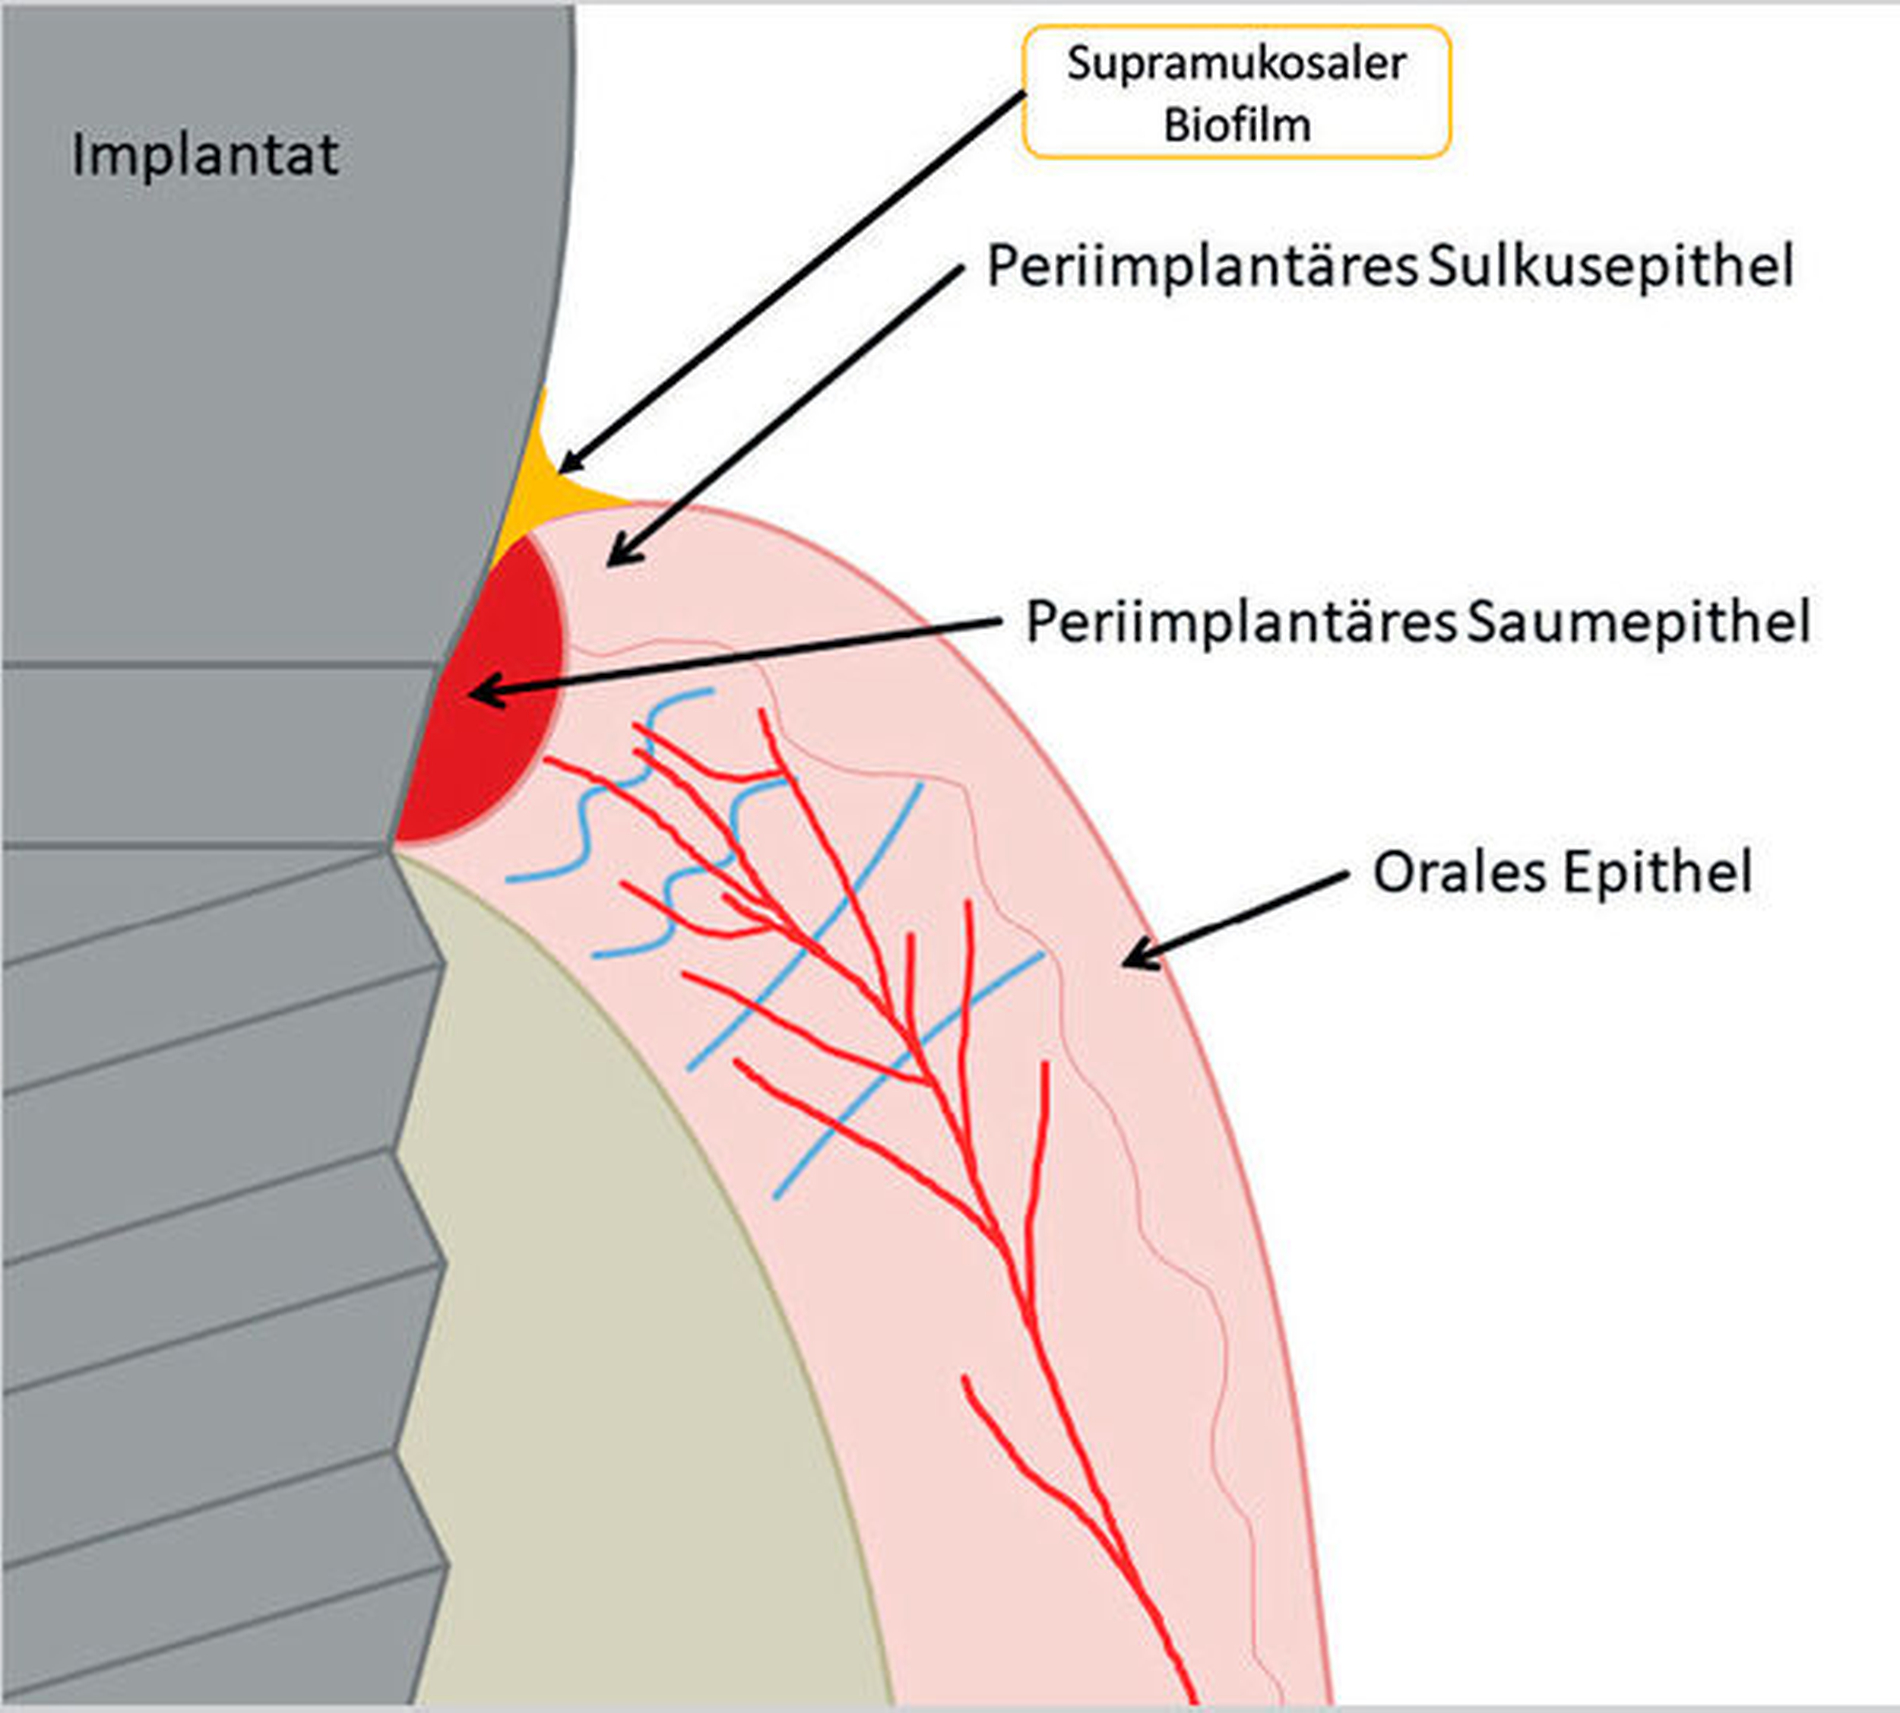

Nach Implantation heilt das dentale Implantat idealerweise ossär ein. Es bildet sich eine Knochen-Implantat-Verbindung aus – eine direkte strukturelle und funktionelle knöcherne Anlagerung an die synthetische Oberfläche des belasteten Implantats [Albrektsson et al., 1981; Albrektsson et al., 1986; Schroeder et al., 1976]. Diese Verankerung ist als Osseointegration bekannt [Branemark et al., 1969; Branemark et al., 1977]. Die periimplantäre Gesundheit ist definiert als klinisch gesundes Hart- und Weichgewebe um ein osseointegriertes Implantat. Dabei kann dies lediglich durch die Abwesenheit klassischer Entzündungszeichen beurteilt werden. Dazu gehören die Abwesenheit von Schwellung, Blutung auf Sondierung und Rötung des periimplantären Weichgewebes [Berglundh et al., 2018].

Kommt es jedoch zur Ausbildung einer Inflammation periimplantärer Gewebe ohne Knochenverlust, spricht man von einer periimplantären Mukositis. Wichtigstes Kennzeichen sind dabei die Blutung auf Sondierung und die Begrenzung der Entzündung auf das periimplantäre Saumepithel [Berglundh et al., 2018]. Breitet sich der pathologische Prozess in den Bereich des knöchernen Attachments aus, ist die Destruktion irreversibel und man spricht von einer Periimplantitis (Abbildung 1a). Zusätzlich zu den bereits genannten klinischen Kennzeichen kann man hier auch röntgenologisch den Knochenverlust feststellen, der mit erhöhten Sondierungstiefen und/oder Rezessionen einhergeht [Berglundh, 2019] (Abbildung 1b).